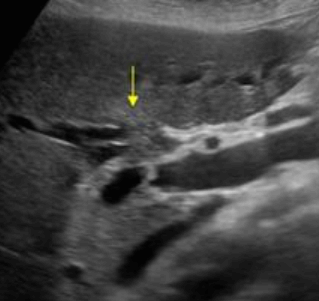

미리찌 증후군 (Mirizzi's syndrom) Mirizzi's syndrom 은 담낭경부, Hartmann's pouch 혹은 담낭관의 결석에 의해 총 간관(CHD)이 폐쇄되는 질환이다. 총 간관(CHD)이 협착되면서 상부담관은 확장되고 하부담관의 직경은 정상으로 나타난다. 증상은 폐쇄성 황달, 복부통증, 발열 등이 나타난다. 급성담낭염이 있으면서 담관폐쇄를 동반할 경우 의심해 볼 수 있다. 담낭절제술 후에 남아있는 담낭관의 결석이 총 간관(CHD)을 직접 누르거나 염증성 협착을 유발하기도 한다.

US finding

- 담낭관 또는 담낭 경부에 결석이 확인된다.

- 총간관(CHD) 또는 담낭관(cystic duct)의 확장소견이 보인다.

- 간내외 담관의 확장이 관찰된다.